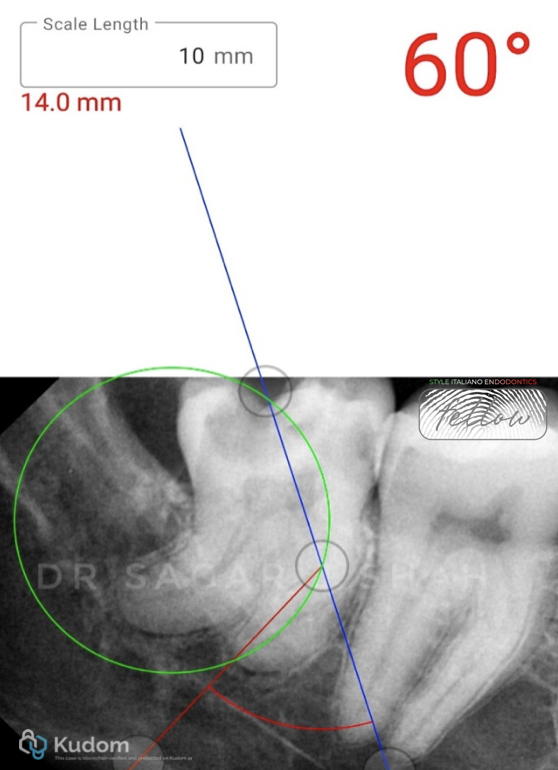

PREOPERATIVE ASSESSMENT:

Mesial canal curvature- 60 degree

The radius of curvature- 14 mm

Close proximity to the mandibular canal.

Pulp calcification was seen with the distal root.

AAE DIFFICULTY ASSESSMENT- HIGH